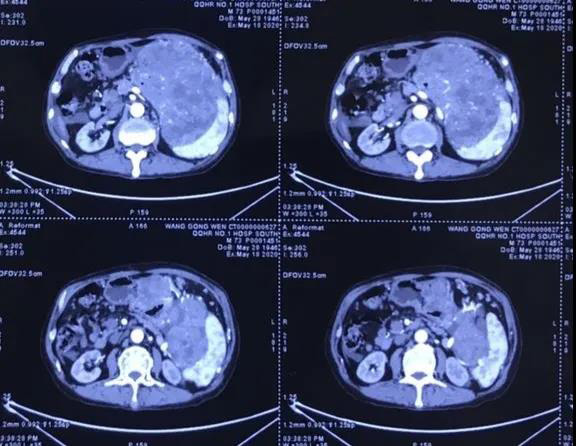

近日,一名年过古稀的患者上腹部胀痛、进食困难20余日,辗转数家医院就医未果,遂抱着试试看的态度来到普外科二病区。经过胃镜、增强CT检查后,提示患者胃占位性病变累及脾脏,胃间质瘤并肝脏转移可能性大。林国英立即组织科室成员进行了详细的术前讨论:患者诊断胃巨大间质瘤明确,考虑合并肝脏转移,理论上应口服药物进行治疗,待瘤体得到控制、减小后,再考虑二期手术治疗。但患者目前已无法进食,瘤体占满了左上腹腔,应及时进行手术治疗,争取切除肝脏转移瘤。但瘤体巨大,血运丰富,且与周围脏器关系密切,尤其脾脏脾门已经受到侵犯。为保证诊疗方案科学适宜,林国英立即组织影像科、输血科、麻醉科、手术室等相关科室专家进行了MDT会诊讨论,最终为患者“量身定制”了一套流程完善、技术完备的手术方案。

术中果然如术前预料般艰难。肿瘤来源于胃底,瘤体占满了整个左上腹腔,前上方与腹壁膈肌固定,左下方横结肠、胰腺、脾脏受压,推向下腹及后腹膜,右上方肝脏受压,推向右上腹,后方与后腹膜固定……整个可操作空间十分狭小,每一步操作都要求术者精细、确切。难度不止于此,瘤体后方几乎不可见,只能依靠手感进行钝行、锐性结合分离,困难程度可想而知。为保证手术的根治性,术中需联同脾脏一并切除,同时切除肝脏三处转移瘤。经历了6个小时的艰苦奋战,手术在多科室的通力配合下圆满完成,术后瘤体总重2400克。